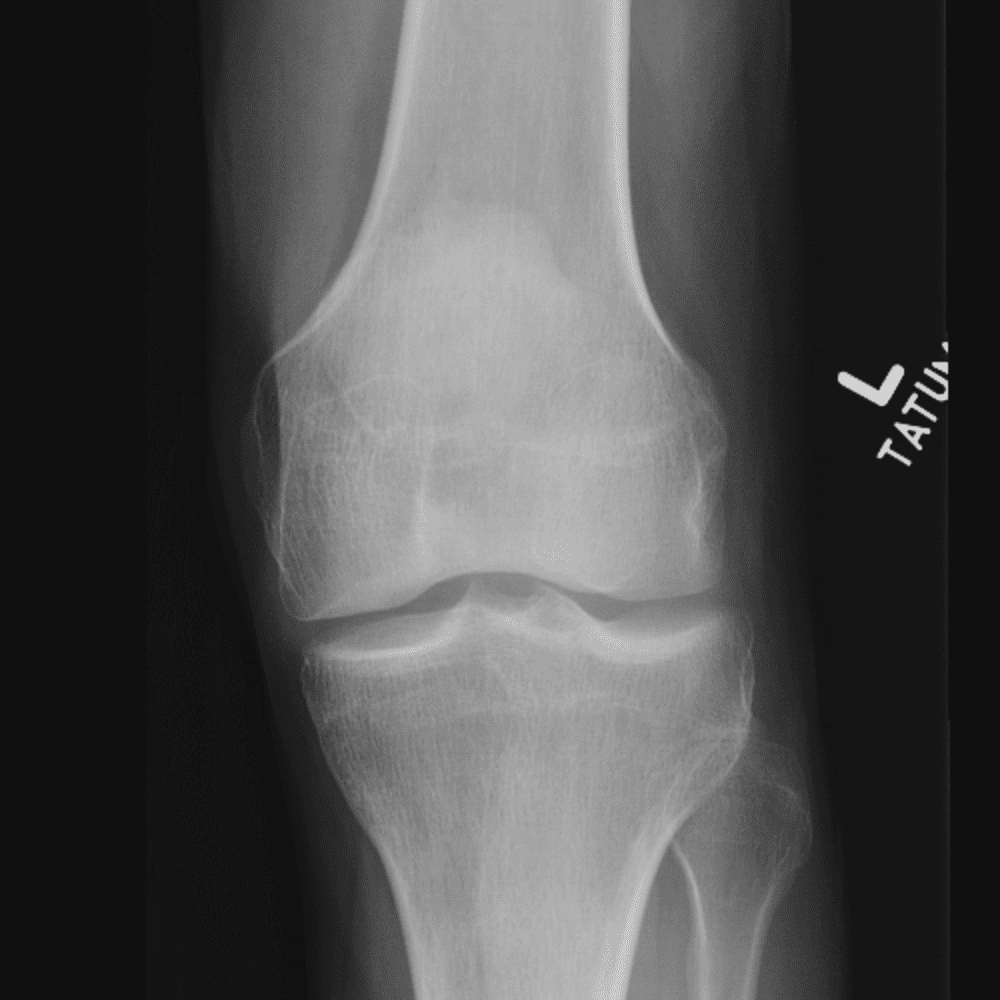

Simula o plantão incluindo casos sutis ou difíceis e alguns normais.